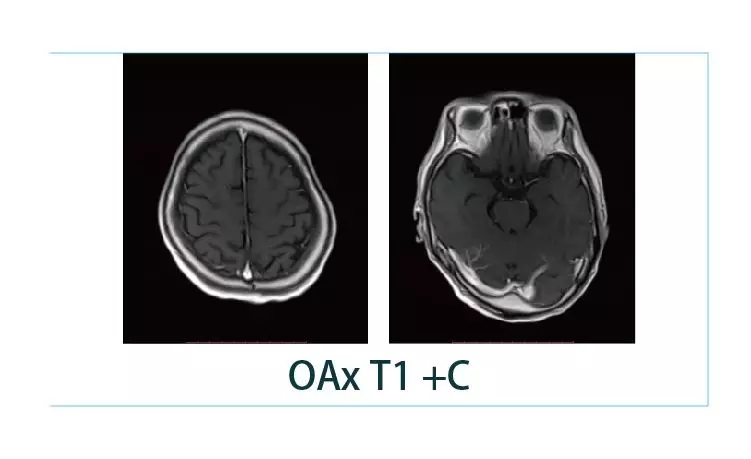

【朗润影像档案】20190125磁共振影像病例结果讨论

1548727074790396.jpg1548727094576003.jpg1548727106975217.jpg1548727127776211.jpg